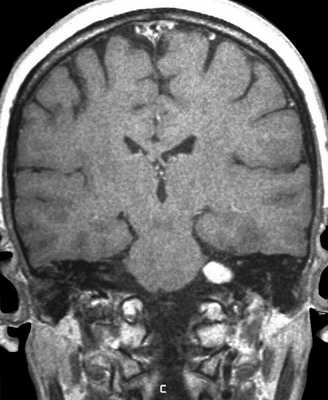

МРТ головного мозга. Т2-взвешенная корональная МРТ. Невринома слухового нерва, цветовая обработка изображения.

Шваннома (невринома) представляет собой инкапсулированную доброкачественную (градация I) опухоль, происходящую из дифференцированных неопластических шванновских клеток оболочек периферических нервов. Растут шванномы медленно и крайне редко малигнизируются. В целом шванномы составляют примерно 8% от внутричерепных опухолей. Пик частоты приходится на возраст 40-60 лет. Чаще всего встречаются шванномы слухового нерва (VIII пара), они составляет около 80 - 90% всех опухолей мосто - мозжечкового угла и около 3% от внутричерепных опухолей. Невриномы происходят из дистального по отношению к входу во внутренний слуховой проход части слухового нерва, обычно из вестибулярной (верхней) его ветви. Двухсторонние невриномы наблюдаются в 5% случаев и связаны с нейрофиброматозом типа II. Поскольку слуховой нерв (VIII пара) и лицевой нерв (VII пара) тесно связаны в начальной части, то на МРТ эти опухоли не дифференцируются. В 7-10% случаев шванноме сопутствует арахноидальная киста. Нейрофибромы отличаются от неврином большим числом соединительнотканных и нервных волокон, а также отсутствием капсулы. Пик частоты приходится на возраст 40-50 лет. Опухоль несколько чаще встречается у женщин. Для неврином слухового нерва характерна сенсоневральная тугоухость, шум в ушах и нарушение равновесия.

На Т2-взвешенных МРТ головного мозга невриномы имеют округлую или овальную форму, изоинтенсивны или слегка гиперинтенсивнее белого вещества, хорошо видны на фоне яркого ликвора цистерны. Крупные опухоли могут подвергаться кистозной дегенерации и включать сосуды. Мелкие невриномы имеют компонент во внутреннем слуховом проходе и как бы “утолщают“ нерв на МРТ изображениях. Как показывает опыт МРТ СПб полностью внутриканальцевые невриномы встречаются редко. МРТ в СПб при шванномах мы проводим обычно с контрастированием. Контрастирование неврином при МРТ с контрастированием хорошее, обычно однородное. Нельзя забывать, что во внутреннем слуховом проходе также может быть воспалительный процесс (неврит), приводящий к сходной клинической симптоматике. При МРТ неврит виден как отёк нерва, имеется контрастное усиление на МР томограммах.

Нейрофиброматоз тип 2. Двухсторонние невриномы слуховых нервов (стрелки). Поперечная Т1-зависимая томограмма с контрастированием.